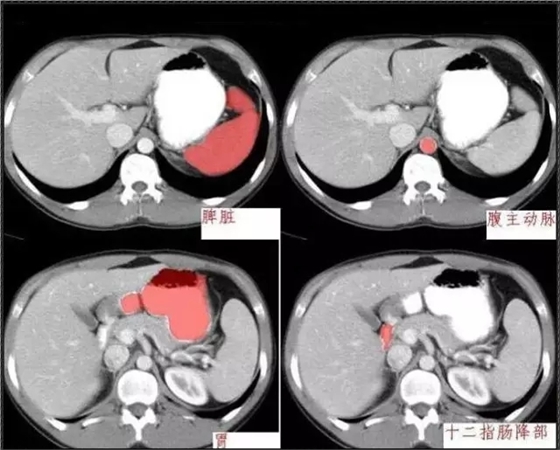

640.webp (3).jpg